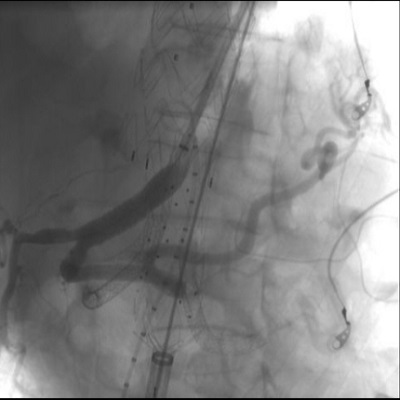

REGGIO CALABRIA Un intervento di elevata complessità è stato eseguito con dalla UOC Chirurgia Vascolare del GOM di Reggio Calabria su un paziente con un voluminoso aneurisma toraco-addominale (7 cm di diametro). L’aneurisma toracico è stato trattato con un approccio endovascolare, mediante il posizionamento di endoprotesi; successivamente è stata posizionata un’endoprotesi ramificata per i vasi viscerali ed una terza endoprotesi aorto-bisiliaca. Il decorso post-operatorio è stato ottimale: il paziente non ha avuto complicanze ed è stato dimesso al proprio domicilio in buone condizioni di salute.

Il complesso trattamento è stato eseguito con successo anche grazie alla collaborazione multidisciplinare dei chirurghi della UOC. Chirurgia Vascolare, diretta dal dr. Pietro Volpe, e del personale della UOSD Terapia Intensiva Post-Operatoria, guidata dal dr. Massimo Caracciolo. L’aneurisma dell’aorta toraco-addominale rappresenta una patologia non molto frequente ma con prognosi molto serie. La patologia richiede un trattamento altamente specialistico a causa del coinvolgimento di tutta l’aorta e dei rami viscerali che da essa originano, che è necessario preservare. Le tecniche endovascolari avanzate consentono di trattare tali patologie complesse che altrimenti prevedrebbero un trattamento chirurgico tradizionale gravato da un elevato tasso di mortalità e da lunghi tempi di degenza in terapia intensiva.